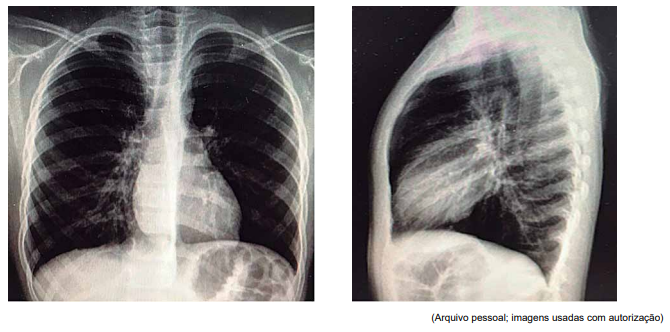

Paciente de 7 anos, com antecedente de asma de difícil controle, deu entrada no pronto-socorro com quadro de um dia de

tosse seca e taquidispneia, sem febre. À admissão, encontrava-se em mau estado geral, com FR = 66 ipm; SatO2

= 85%,

em ar ambiente, com sibilos inspiratórios e expiratórios à ausculta, com tiragens de fúrcula intercostal e subdiafragmática

graves. Foram realizadas as radiografias de tórax a seguir.

Não houve resposta com as medidas adotadas, evoluindo com tórax silente e bradipneia, sendo indicada intubação. Foi transferido, então, à UTI pediátrica com os seguintes parâmetros ventilatórios: em pressão controlada (modo assistido- -controlado), com pressão positiva expiratória final (PEEP) = 8; frequência respiratória (FR) = 28 ipm; pressão inspiratória (Pinsp) (acima do PEEP) = 13; tempo inspiratório (Tins) = 0,7 s; fração inspirada de oxigênio (FiO2 ) = 100%, com assincronia ventilatória e saturação limítrofe.

Em face do exposto, assinale a alternativa que descreve, corretamente, os ajustes que devem ser realizados na ventilação.

Não houve resposta com as medidas adotadas, evoluindo com tórax silente e bradipneia, sendo indicada intubação. Foi transferido, então, à UTI pediátrica com os seguintes parâmetros ventilatórios: em pressão controlada (modo assistido- -controlado), com pressão positiva expiratória final (PEEP) = 8; frequência respiratória (FR) = 28 ipm; pressão inspiratória (Pinsp) (acima do PEEP) = 13; tempo inspiratório (Tins) = 0,7 s; fração inspirada de oxigênio (FiO2 ) = 100%, com assincronia ventilatória e saturação limítrofe.

Em face do exposto, assinale a alternativa que descreve, corretamente, os ajustes que devem ser realizados na ventilação.